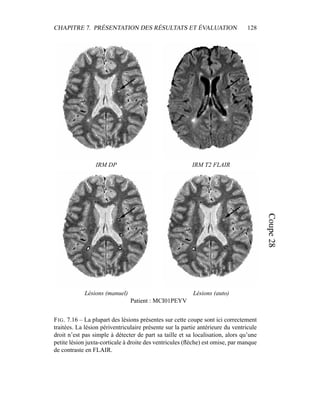

Pour éliminer dans un premier temps l’influence des lésions de SEP, un témoin

a été choisi pour cet exemple, et les résultats sont présentés dans la figure 4.5. Pour

la segmentation du masque du cerveau, seule la segmentation était intéressante.

Une mauvaise estimation des paramètres de classes, ou un mauvais modèle était

sans importance tant que la segmentation était valide. Par contre, dans le cas de la

segmentation en tissus, avoir une bonne estimation des paramètres est primordial,

car c’est à partir de là que les lésions de SEP vont être segmentées. Pour obser-

ver la qualité de la segmentation dans la figure 4.5, il faut donc en permanence

regarder deux espaces reliés.

– L’espace des intensités : visualisé via l’histogramme conjoint entre les deux

modalités, il est représenté par les paramètres de classes µk et Σk. Une mé-